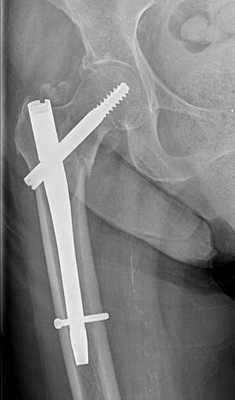

Внутреннюю лодыжку фиксируют двухлопастным гвоздем или винтами. При разрывах межберцового синдесмоза производят сближение берцовых костей, используя длинный винт или специальный болт. Для фиксации наружной лодыжки применяют гвоздь или спицу. При переломах заднего и переднего края производят остеосинтез лодыжек винтом или гвоздем. Затем рану послойно ушивают и дренируют, на ногу накладывают гипс. В послеоперационном периоде проводят антибиотикотерапию, назначают анальгетики, УВЧ и лечебную физкультуру. После снятия гипса осуществляют мероприятия по разработке сустава.

При переломе лодыжек выполняется оперативное вмешательство называемое: открытая репозиция и внутренняя фиксация, или остеосинтез. Для доступа к сломанной кости выполняются разрезы вне проекции крупных сосудисто нервных пучков.

Сломанная кость обнажается, производится сопоставление костных отломков, временная фиксация при помощи костодержателей, спиц, костных цапок. Далее выполняется остеосинтез при помощи пластин и винтов. Временная фиксация удаляется.

Клинический случай 1. Перелом обеих лодыжек с подвывихом стопы кнаружи.

44 В2-2

Пациентка Т. 80 лет. Травма за 3 недели до обращения, получила перелом обеих лодыжек правой голени со смещением, подвывихом стопы кнаружи. Обратилась в РТП, выполнена рентгенография, наложена гипсовая повязка. В связи с сохраняющимся выраженным отёком и болевым синдромом обратилась в клинику К+31.

На рентгенограммах в гипсе определяется значительный подвывих таранной кости кнаружи, консолидирующийся перелом нижней трети малоберцовой кости.

В день обращения пациентка послоностью обследована, проведено оперативное лечение, открытая репозиция, остеосинтез перелома нижней трети малоберцовой кости пластиной, внутренней лодыжки винтом, внутренняя лодыжка дополнительно фиксирована анкерным фиксатором.

На контрольных рентгенограммах после операции положение отломков, металлофиксаторов правильное, подвывих таранной кости устранён.